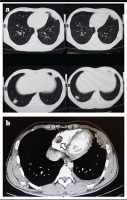

Multiple areas of consolidation were noted on CT, with no significant interval changes compared to prior imaging (Figure 1a). Lower limb venous Doppler was not performed due to the absence of clinical signs suggestive of deep vein thrombosis, such as leg swelling or pain. But considering the patient’s recent hospitalization, ongoing tachycardia, and hemoptysis, along with a Wells score indicating a high likelihood of pulmonary embolism, a CT pulmonary angiography (CTPA) was performed to evaluate for possible thromboembolic events. CTPA identified filling defects in the segmental branches of the pulmonary arteries as well as in the right ventricle (RV) (Figure 1b). Additionally, multiple areas of consolidation were noted, with no significant interval changes compared to prior imaging.

Figure 1

a) Chest CT (axial view) showing bilateral patchy subpleural consolidations in the lingula and lower lobes, consistent with vasculitis-related inflammation; b) CTPA (axial view) demonstrating filling defects in segmental and subsegmental pulmonary artery branches bilaterally and a thrombus in the right ventricle (arrow)